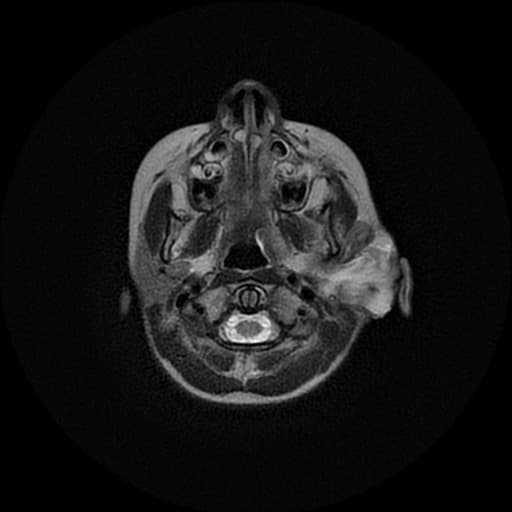

Axial T1 C+ fat sat

Di căn nội sọ

Đau đầu mới xuất hiện và liệt nửa người trái ở bệnh nhân đang điều trị ung thư phổi tế bào không nhỏ.

Phát hiện nhiều nốt (nodule) và khối (mass) ở vùng trên lều, trong đó tổn thương lớn nhất nằm ở thùy chẩm phải, kích thước khoảng 34 x 29 x 30 mm.

Tổn thương được bao quanh bởi phù quanh tổn thương (perilesional edema), tín hiệu không đồng nhất (heterogeneous signal intensity) — chủ yếu giảm tín hiệu trên T1W, tăng tín hiệu trên T2W và FLAIR, kèm hạn chế khuếch tán nhẹ (mild diffusion restriction).

Ghi nhận các ổ giảm tín hiệu rải rác trên GRE.

Sau tiêm thuốc tương phản, tổn thương cho thấy tăng quang (enhancement) mạnh, không đồng nhất.

Có hiệu ứng chiếm đoạt không gian (mass effect) với chèn ép chai thể (corpus callosum) bên phải và não thất bên phải.

Dày bất thường màng não (meninges) vùng trán trái, độ dày tối đa đến 12 mm, có tăng quang rõ sau tiêm gadolinium.

Bất thường tín hiệu ở xương trán trái, biểu hiện giảm tín hiệu trên cả T1W và T2W, kèm tăng quang rõ sau tiêm gadolinium.

Dịch ứ đọng trong xoang trán trái.

Các tổn thương ở nhu mô não (brain parenchyma), sọ vòm (calvarium) và màng não (meninges) vùng trán trái phù hợp với di căn nội sọ (intracranial metastases).

Di căn nội sọ (intracranial metastases)

- "Di căn nội sọ thường bắt nguồn từ ung thư phổi, vú, melanoma, thận và đại tràng."

- "Di căn màng não mềm (leptomeningeal) có thể biểu hiện bằng hình ảnh tăng quang lan tỏa màng não và các tổn thương thần kinh khu trú."

- "Di căn sọ vòm thường xuất hiện dưới dạng tổn thương giảm tín hiệu trên cả T1 và T2, tăng quang mạnh sau tiêm thuốc tương phản."